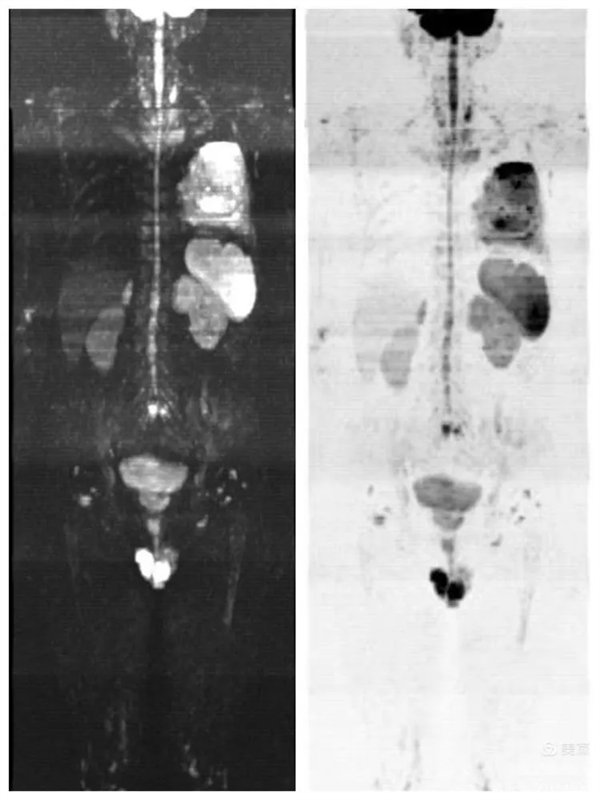

患者,男,左肺病變,為了查找全身有無其它病灶,明確分期,制定最合適的診療方案,臨床醫生決定行“類PET”即全身磁共振彌散成像(WB-DWI)檢查。

圖3:全身彌散成像偽彩圖

磁共振全身彌散加權成像(WB-DWI),是將彌散加權成像技術與自動拼接技術和全景成像矩陣相結合而獲得全身的彌散加權成像影像。所得影像經黑白翻轉后可達到與正電子發射計算機體層顯像(PET)影像類似的效果,故被稱為“類PET”,是近年來發展起來的全新影像檢查新技術。

該技術能夠進行全身大范圍掃描,并加以3D后處理重建,可獲得全身腫瘤篩查、良惡性腫瘤的鑒別、腫瘤TNM分期及療效隨診等診斷信息,全身彌散技術把肌肉、脂肪、肝臟等組織背景信號抑制掉,突出了病變的顯示,大大提高了病變組織尤其是惡性腫瘤及其轉移灶的檢出率。